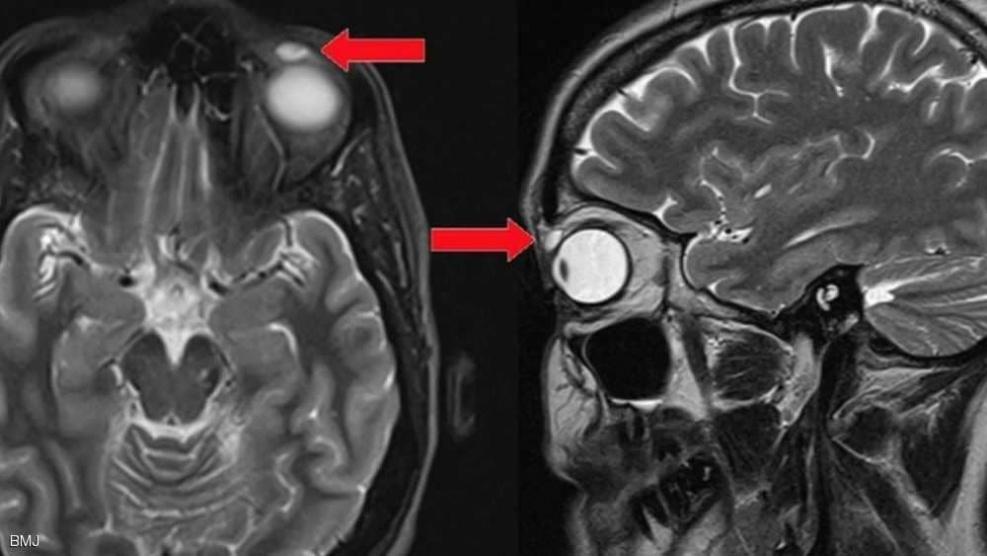

شبكة وتر-حين فقدت امرأة بريطانية، عدسة عين لاصقة، قبل 28 سنة، خلال مباراة للعبة الريشة الطائرة، لم يتمكن الأطباء من العثور على القطعة الضائعة، لكن الضحية اكتشفت مؤخرا أن العدسة انزاحت فقط صوب الجانب الأيسر من الجفن.

وأظهر فحص بالأشعة أن المشكلة الصحية ناجمة عن وجود عدسة يناهز حجمها 8 ميليمترات، وهو ما جعل الطبيب يلجأ إلى الجراحة لإزالة العدسة التي ظلت في مكانها قرابة ثلاثة عقود.